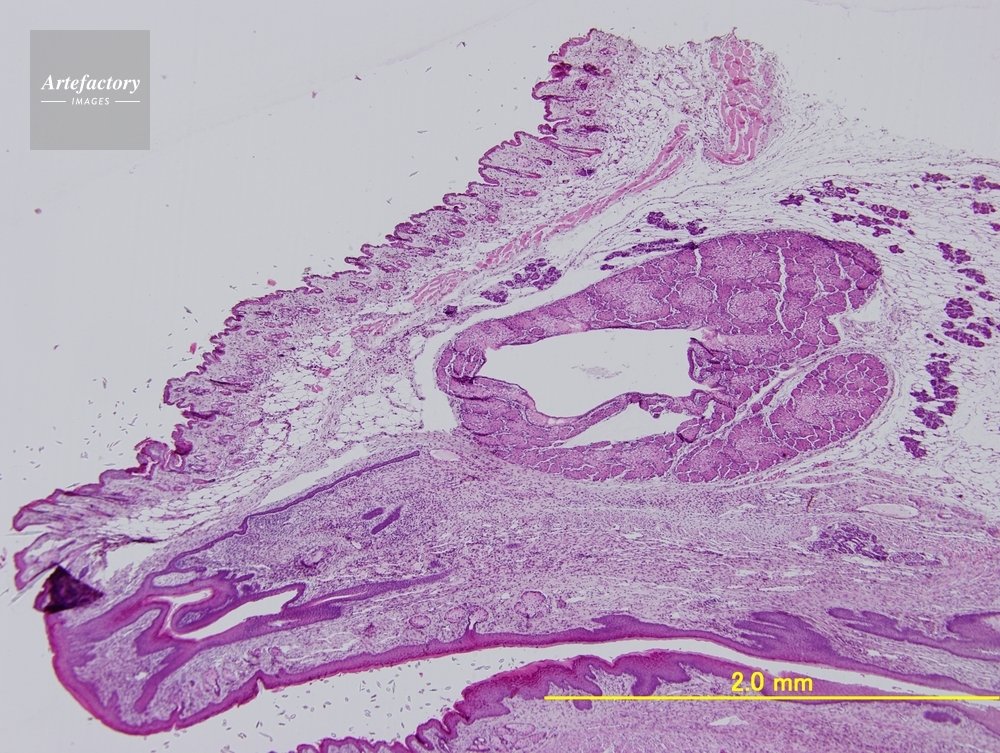

| 作品タイトル | マウス 膣、子宮、直腸 | モデルリリース | なし | |